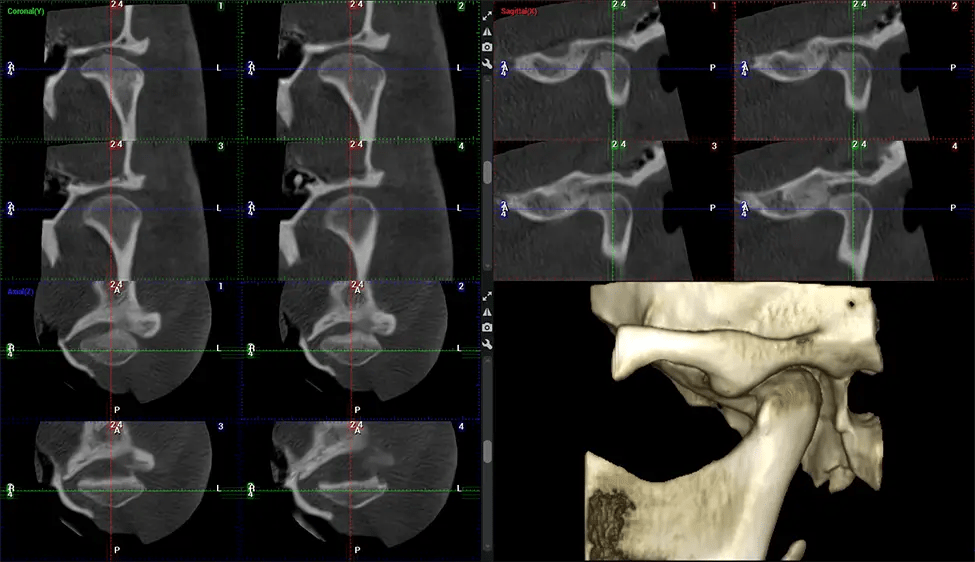

Oral and Maxillofacial Surgeon Complex oral surgeries, orthognathic (jaw) surgery, and removal of impacted teeth. Offers precise, three-dimensional visualization of the skull, jaw, and craniocervical junction to enhance diagnostic accuracy and minimize surgical risks.

Orthodontist Assessing facial asymmetry, planning orthognathic surgery, and managing cleft lip and palate and sleep apnea. Provides a comprehensive view of the craniofacial complex to better plan treatments and evaluate outcomes.

Upper Cervical Chiropractor Diagnosing structural problems in the C1-C2 vertebrae, assessing misalignment and instability, and evaluating chronic pain. Enables precise, weight-bearing views of the upper cervical spine, helping to identify abnormalities that inform targeted, non-invasive therapies.